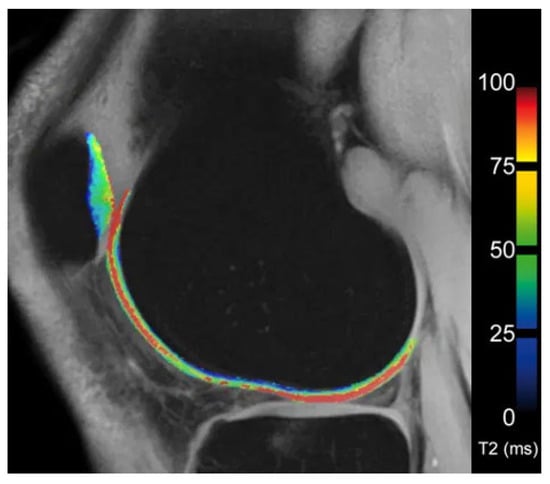

The articular cartilage matrix comprises a collagen network and proteoglycans (PG). Early stages of OA have been shown to exhibit disruption of that matrix with a concomitant decrease in water and proteoglycans in cartilage [68]. This decrease in water content can be noticed as alteration in T2-weighted images, albeit with a lack of sensitivity [69]. Lüsse et al. demonstrated a greater sensitivity of T2-relaxation-time measurements, known as T2 mapping, for minimal changes in cartilage [70]. Several studies have confirmed the diagnostic accuracy of the technique [71]. Images are acquired via a multiecho spin echo technique to measure T2 values. Those are displayed as a grayscale or color-encoded map highlighting areas at risk for OA (Figure 5) [42,70]. T2 maps can be acquired with most commercially available scanners. However, as Koff et al. demonstrated, T2 measurements do not correlate with manifestation of OA as seen on radiography, and thus are limited for early-stage detection of OA [72].

Figure 5 was kindly provided by Siemens Healthineers without influence on the content of this review.

Figure 5. T2 map of femoral and patellar cartilage in the knee (Image kindly provided by Siemens Healthineers). The colorbar on the right indicates the T2 relaxation time.